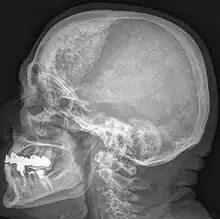

| Hyperostosis frontalis interna in a 74-year-old woman | |

Hyperostosis frontalis interna is a common, benign thickening of the inner side of the frontal bone of the skull. It is found predominantly in women after menopause and is usually asymptomatic. Mostly frequently it is found as an incidental finding discovered during an X-ray or CT scan of the skull.